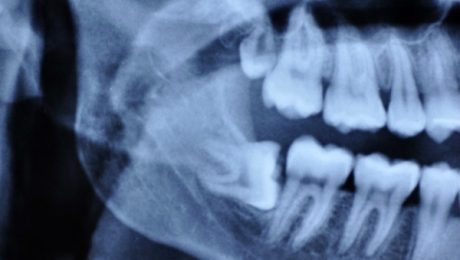

جراحی دندان عقل نهفته با لیزر چگونه است؟

دندان عقل یا دندان های آسیاب سوم همانند دیگر دندان ها و یا حتی بیشتر دارای اهمیت است. اما به سبب روند رشد طولانی و نفوذ کردن از بافت لثه بیشتر از دیگر دندان ها در معرض مشکلات قرار می گیرد طبق تعریف ارتودنسی دندان عقل نهفته، دندان خارج نشده ای است که به دلایل

کشیدن دندان عقل یک روش جراحی برای حذف یک یا چند دندان عقل است-چهار دندان بالغ دائمی که در گوشههای دهانتان در بالا و پایین قرار دارند. اگر دندان عقل جا برای رشد نداشته باشد(دندان عقل تحت فشار)، باعث درد، عفونت و سایر مشکلات دندانی میشود و احتمالأ لازم است که آن را بکشید. کشیدن

ضرورت کشیدن دندان عقل | آيا لازم است دندان عقلم را بكشم؟

در حالي كه دندانتان مشكل خاصي ندارد, دندانپزشك به شما مي گويد كه بايد دندان عقل تان را بكشيد. سوال اينجاست كه ضرورت کشیدن دندان عقل چیست؟ اين روزها , جراحي دندان عقل يك عمل استاندارد است و تقريبا يك مرحله گذرا براي جوانان است كه البته هميشه ضرورت ندارد که براساس يك مطالعه ,هر